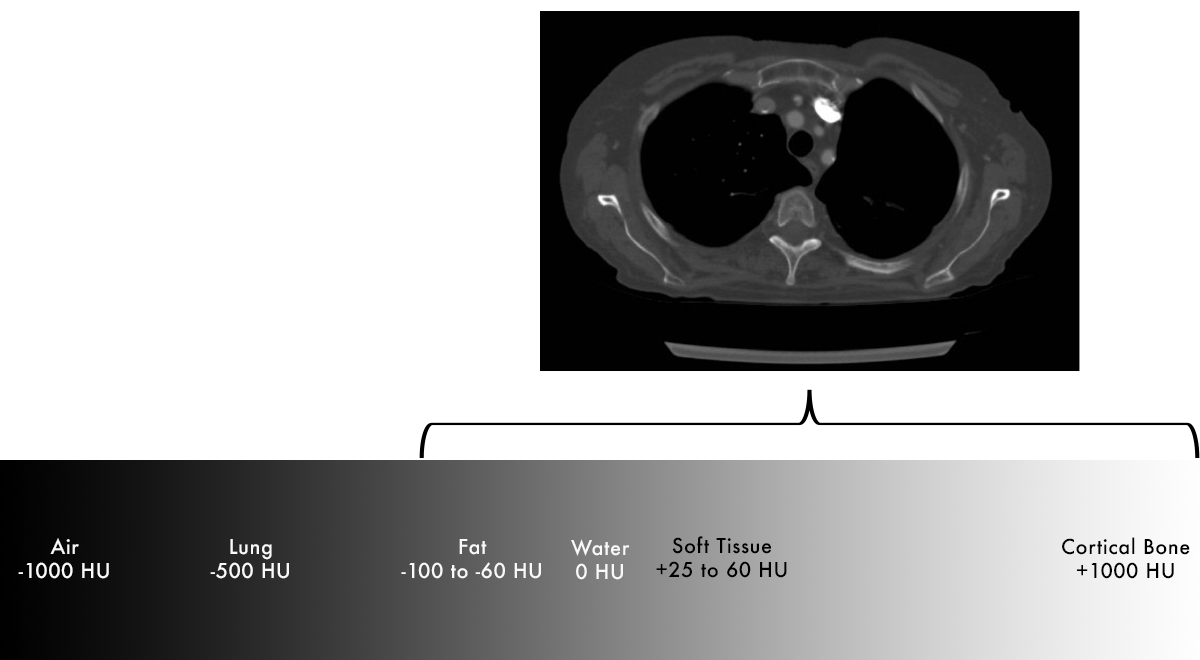

Density

- Dense material absorb x-rays and prevent them from reaching the detector.

- Air – does not absorb many x-rays – most reach detector – appears dark.

- Bone – absorbs more x-rays – few reach detector – appears light on image.

- In CT, we are able to measure the amount of x-rays that are transmitted (pass through) to the detector to get a value corresponding to the density of the material.

- Tissue density is measured in Hounsfield units (HU).

Hounsfield Units

Definition

- Water = 0 HU

- Air = -1000 HU

- Everything else = scaled based on density relative to air/water

Air < Fat < Fluid < Soft tissue < Bone < Metal

Fat

- Fat is less dense than water, negative HU

- Fat floats on water – easy way to remember this.

Soft Tissue and Blood

- Soft tissue is mostly intracellular water, but also contains additional substances (connective tissues) that raise the density slightly

- Positive HU, but not far from water (+25 to +60)

Lung

- Lung is a mixture of soft tissue and air – overall density of lung falls between these two values

Bone

- Cortical bone – extremely dense – highly positive HU (+1000)

- Medullary bone – mix of dense bone and soft tissue (+300)